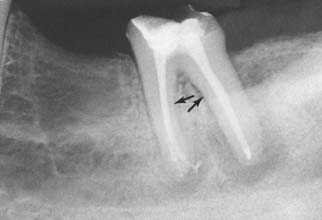

Relatively long posts with a circular cross-section provide good retention and support in anterior teeth but should be avoided in posterior teeth, which often have curved roots and elliptical or ribbon-shaped canals (Fig. 12-19). For these teeth, retention is better provided by two or more relatively short posts in the divergent canals.

Fig. 12-19 When preparing posterior teeth for intracoronal retention, the practitioner must be careful to avoid perforation, especially on the distal surface of mesial roots and the mesial surface of distal roots, where residual tooth structure is normally thinnest and where concavities are often present (arrows).